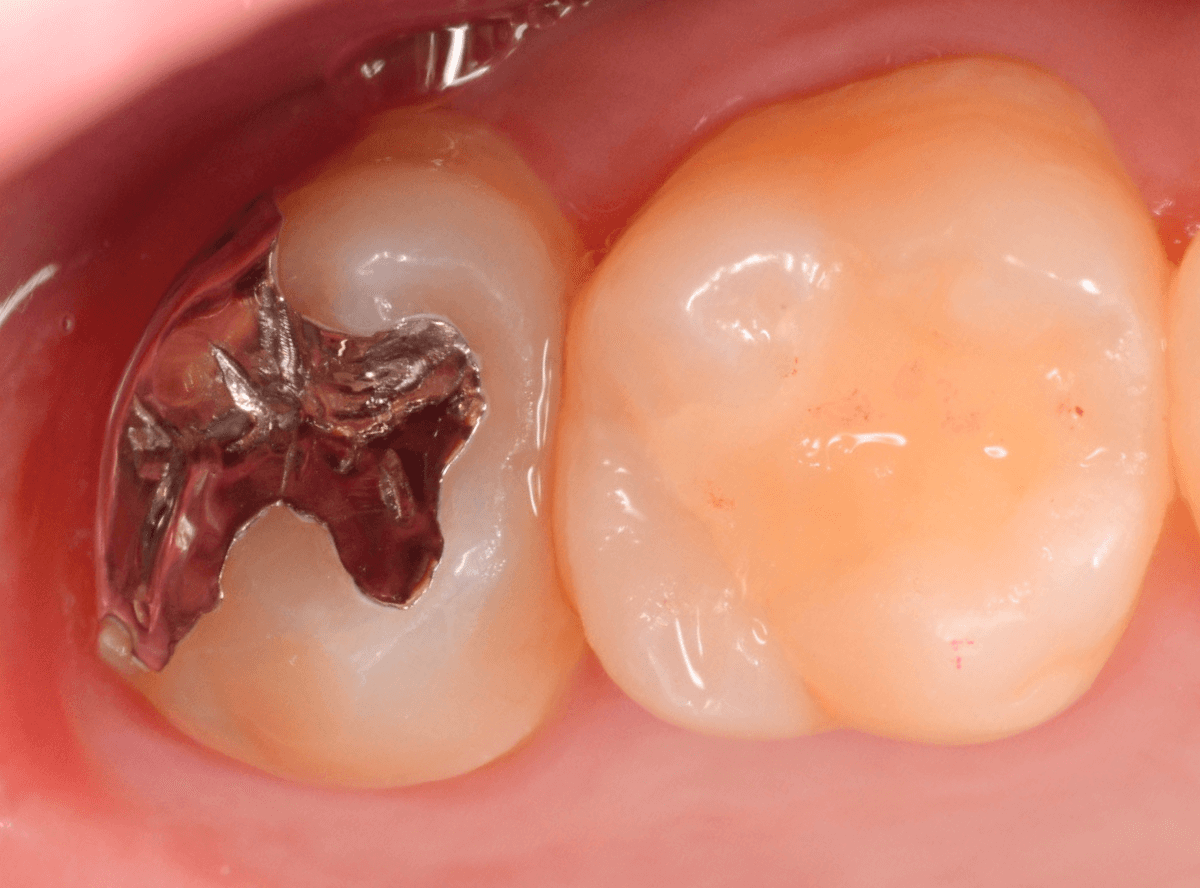

Case.4 2年間メンテナンスを中断している間に、深く虫歯が進行!

定期メンテナンスを2年間中断後に、来院された患者さんです。

見た目は手前の歯との間の小さな虫歯に見えますが、

「普段は痛くない」

「食事の時に物がつまる」

「物がつまった時に噛むと痛い」

・・・と、自覚症状は乏しいが、実際は大きな虫歯の場合の症状あるあるの訴えでした。

レントゲン写真で虫歯の状況を確認します。

赤い線が虫歯の部分、青い線が歯の神経の部分です。

思った通り、入り口の小さなすき間の中は、神経まで達してしまいそうな大きな虫歯になっていました。

歯を削り始めると、すぐに大きな穴が出てきました。

ある程度虫歯を除去したところで、う蝕検知液で染め出してチェックします。

まだまだ虫歯が残っていますね。

取り残しがないように、しっかり除去する必要があります。

虫歯を全て除去したところです。

神経が少し見えるところまで虫歯が進行していました。

神経を保護するお薬をつめた後、蓋をしてしばらく痛みが出ないか、経過観察します。

痛みが出て止まらないようでしたら、神経を除去する治療が必要になります。

定期メンテナンスを中断しなければ、このような状況にはならなかった事が本当に悔やまれます。

しばらく経過観察後、幸運にも特に症状なく経過しましたので、型どりをして、つめもの(メタル・インレー)で修復する事ができました。

この後、サボらず定期メンテナンスに来院いただくよう、念を押して治療終了となりました。